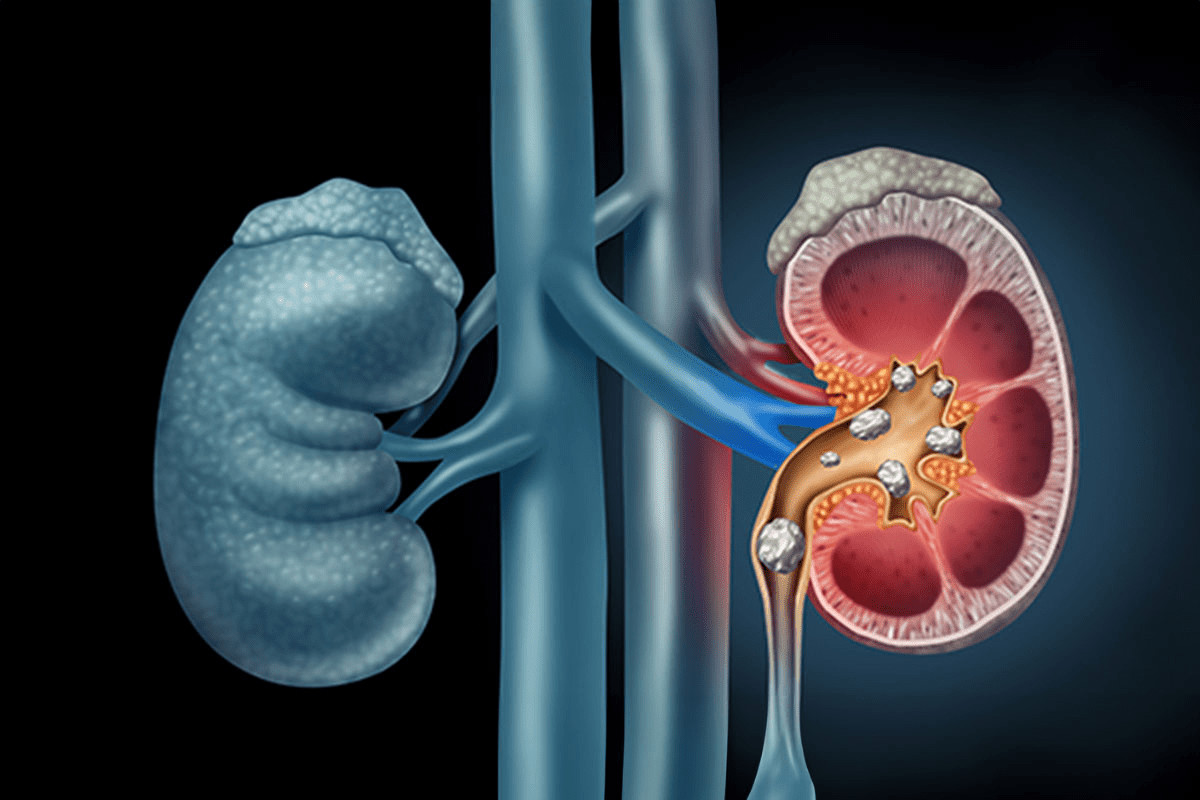

Calcium oxalate stones are the most common type of kidney stone. They form when calcium and oxalate in urine combine. This mix can create small crystals that grow into stones. Factors like diet, how much you drink, and your genes can affect their formation.

To understand dark kidney stones, we need to look at how they form. Stones happen when urine has too much stuff that forms crystals. This is why calcium oxalate stones are so common.

The process starts when urine has too much of certain substances. This can be due to not drinking enough water, what we eat, or our genes. When there’s too much, crystals start to form.

Many things affect how crystals form, like the urine’s pH and other substances. Calcium oxalate monohydrate is a key type that shapes the stone’s makeup.

Calcium oxalate monohydrate is a big part of many stones. It forms when calcium and oxalate in urine mix right. This creates crystals that can grow into stones.

The presence of calcium oxalate monohydrate makes some stones harder to treat. This is because of their hardness and other traits.

Crystals start small and grow into stones over time. First, tiny crystals form in the urine. If they keep growing, they can block and cause pain.

Knowing how this happens helps us prevent stones. By stopping crystals from growing, we can lower our risk of getting dark kidney stones.